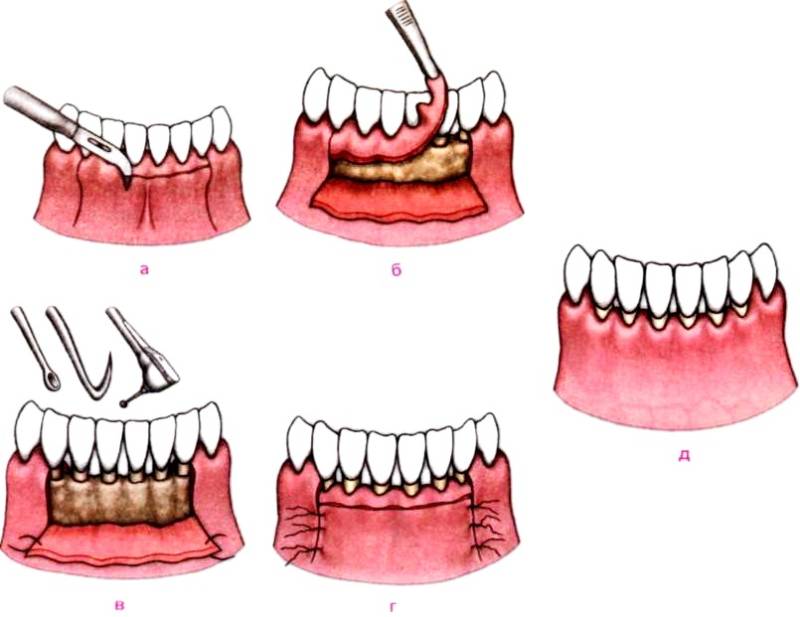

Процедура відкритого кюретажу

За допомогою цієї методики не тільки усуваються грануляції і відкладення, але і відновлюється кісткова тканина. Відкритий кюретаж виконується, якщо глибина пародонтальної кишені знаходиться в інтервалі 3-5 мм, що відповідає середній або сильному ступені захворювання. В даному випадку мається на увазі відділення ясна від стінок зуба.

Етапи проведення відкритого кюретажа.

Попередньо необхідно проведення підготовчої роботи, яка включає в себе:

- видалення зубних відкладень;

- терапію запального процесу;

- при необхідності – шіннірованіе зубів.

Потрібну ділянку знеболювальні за допомогою місцевої анестезії. Потім виконується безпосередньо процедура відкритого кюретажу. Вона виглядає наступним чином:

- Після надрізу в пришийковій області ясна відшаровується від зуба і кістки на всьому необхідному просторі.

- Проводиться візуальний огляд кісткової тканини і коренів.

- За допомогою спеціальних пристосувань (ультразвукового скалера, хірургічних кюрет) видаляються всі відкладення і некротичні маси.

- Оброблена область ретельно промивається антисептиками.

- В необхідних випадках робиться підсадка синтетичної кістки.

- Розкритий і оброблений кишеню вшивається, і накладається ясенна пов’язка.

Після проведення процедури, до зняття швів, пацієнту потрібно проявляти особливу обережність. Це стосується виконання гігієни порожнини рота і прийому їжі. Зняття швів зазвичай відбувається після закінчення 10 днів.